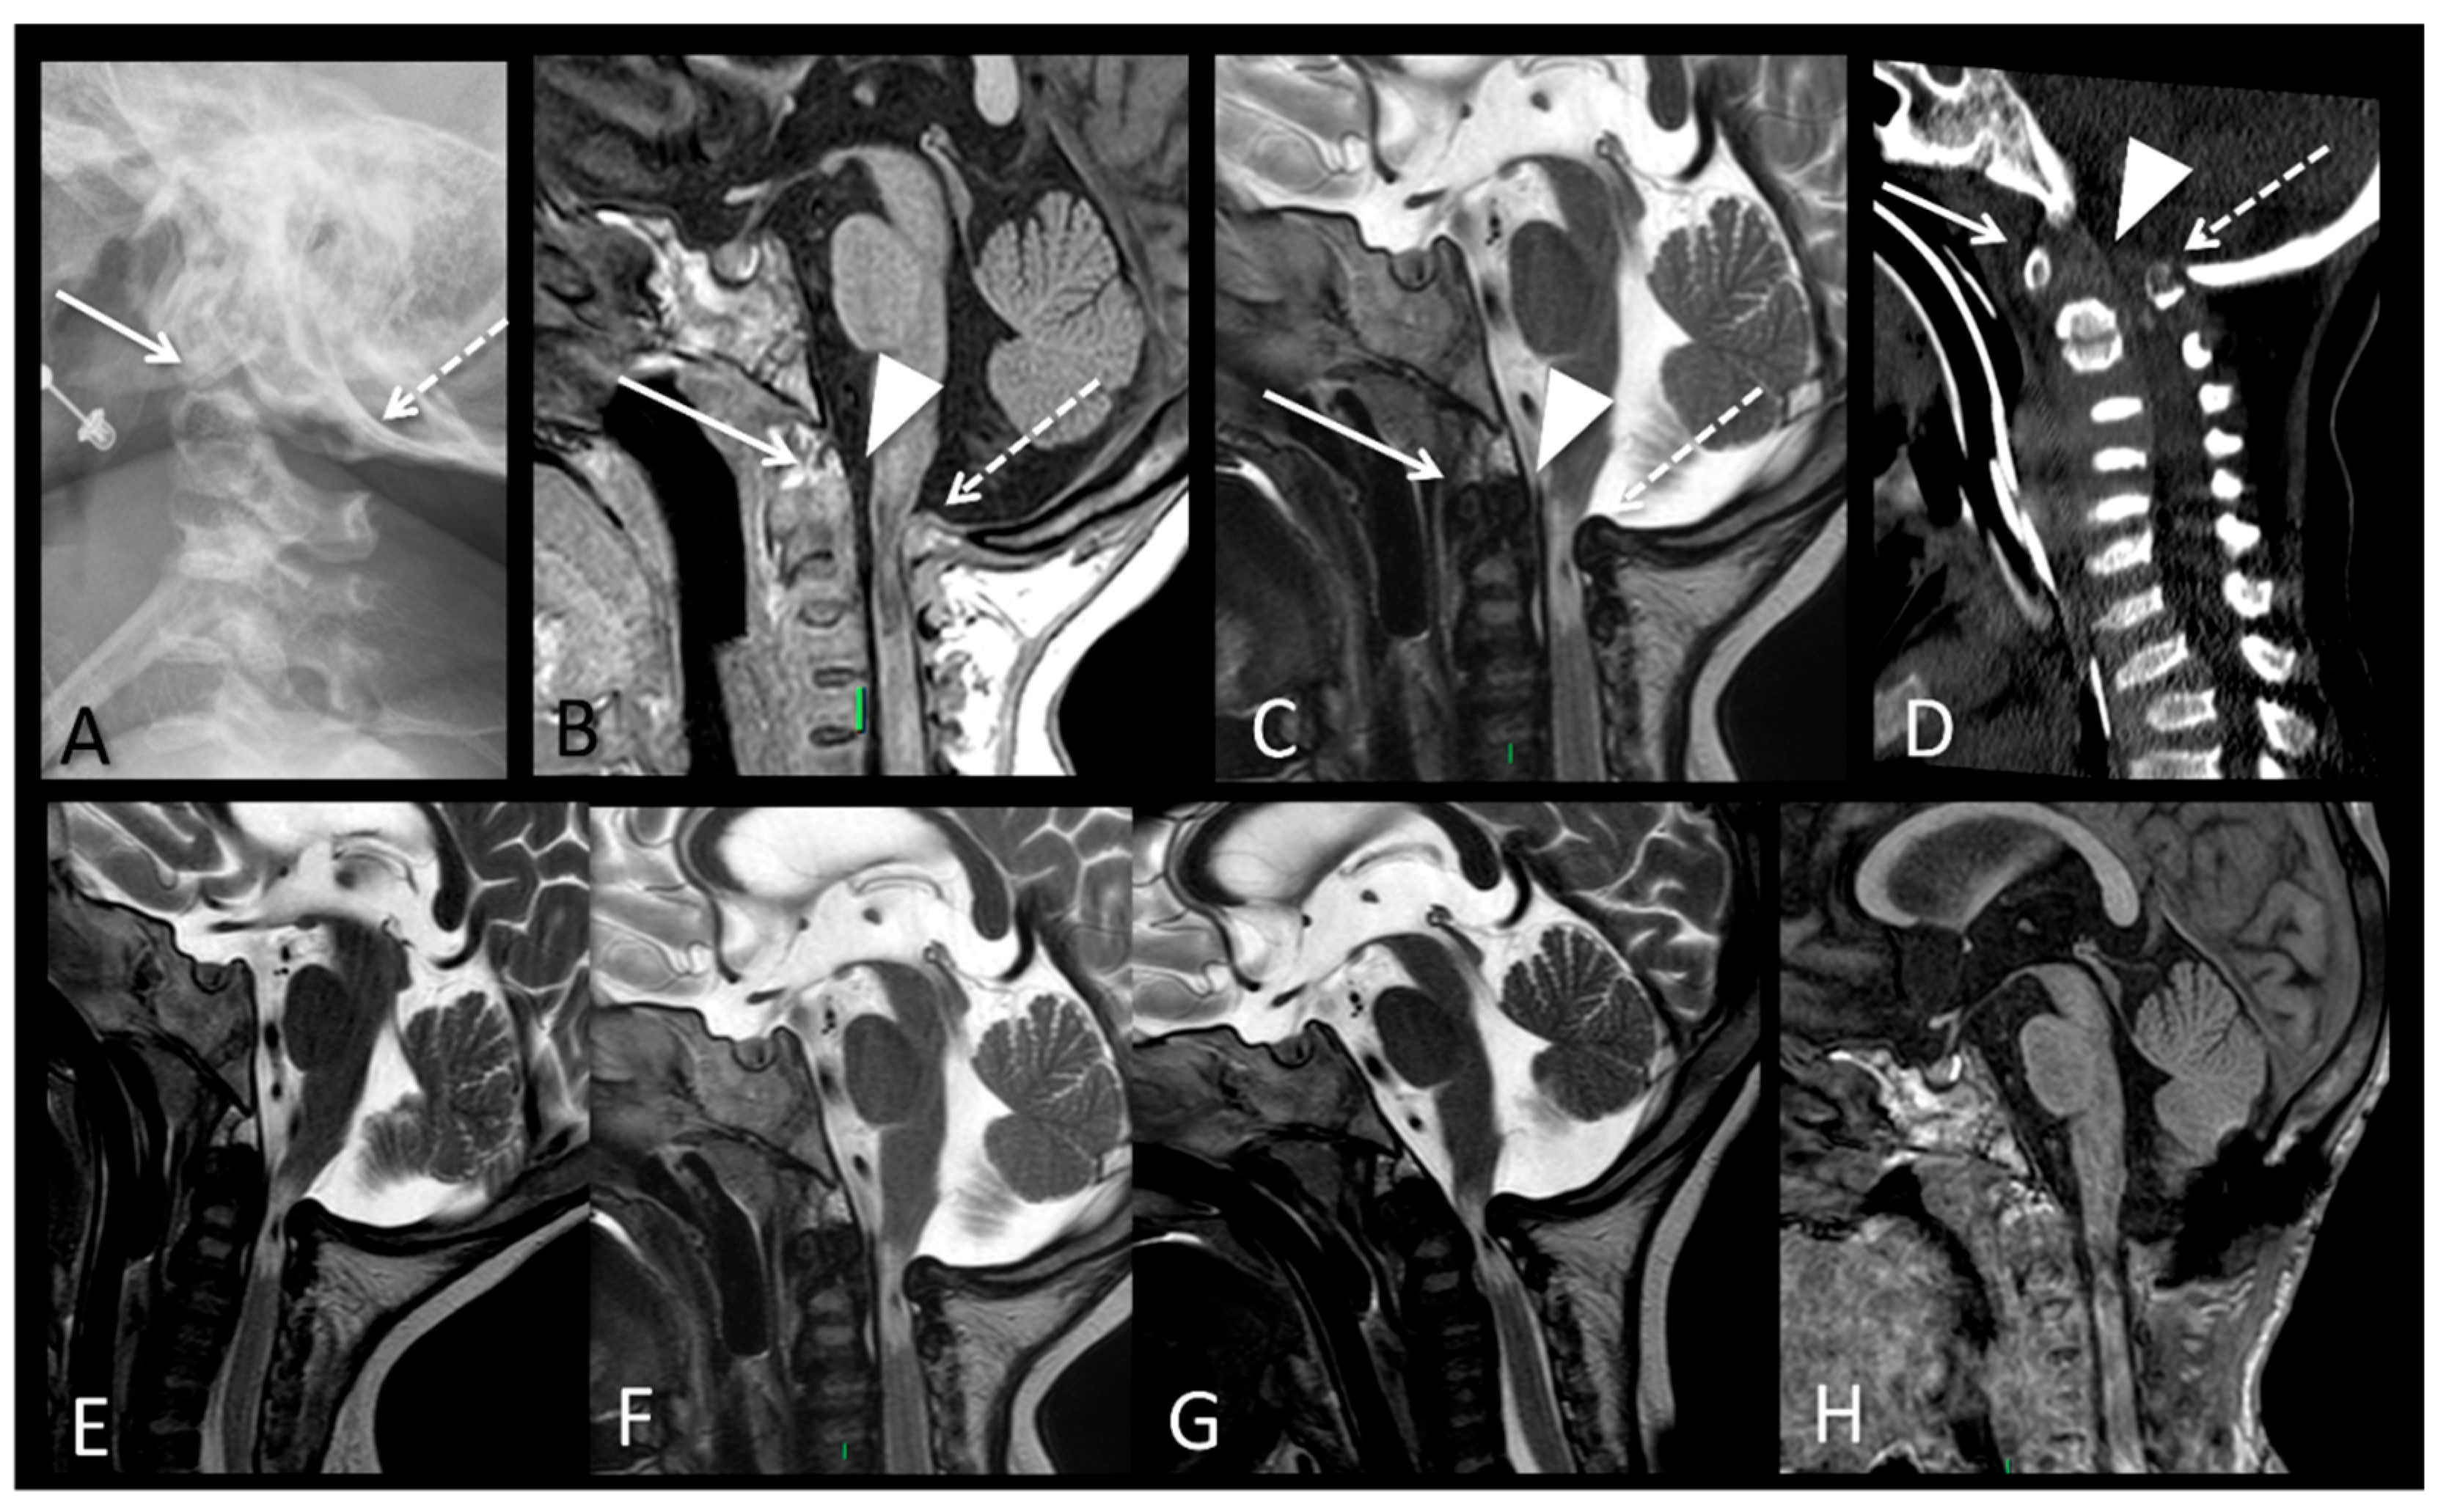

| Spinal canal/ foramen magnum stenosis | N.A. | + | + | + | + | |||

| Odontoid hypoplasia | N.A. | + | + | + | + | |||

| Compressive myelopathy | N.A. | + | + | + |

| P2 (MPSII) | Baseline | RX and MRI | Spine | Vertebral body deformities; posterior bulging of the intervertebral discs. |

| After 6 years of ERT | RX and MRI | Spine | Thoracolumbar kyphosis; anterior beaking and posterior scalloping of vertebral bodies. | |

| MRI | Brain | Extension of the white matter signal alterations; severe dilation of the ventricular system; cerebral atrophy. | ||

| After 8 years of ERT | MRI | Spine | Deformities of the vertebral bodies and posterior bulging of the intervertebral discs; spinal canal impression. |